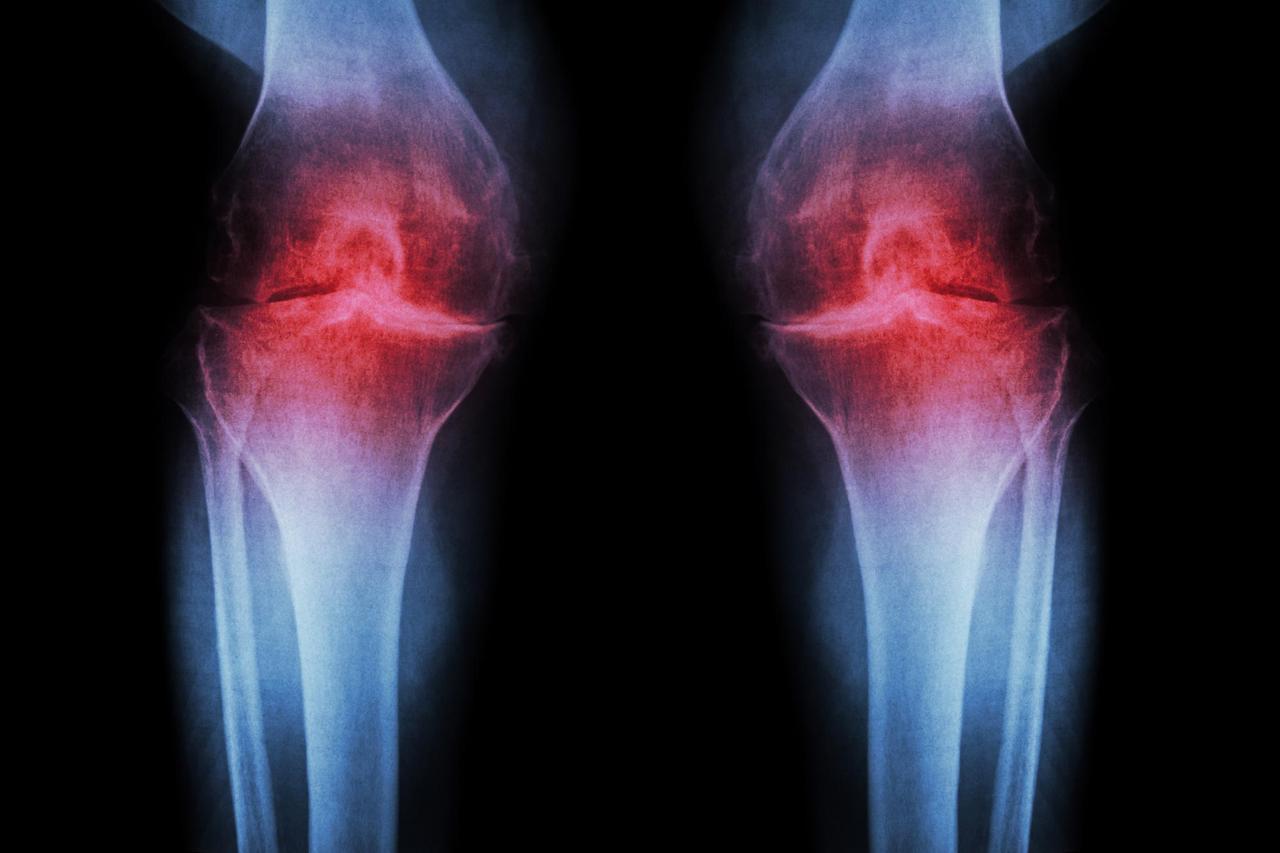

Любителям пожаловаться на коленки учёные нашли способ заново вырастить хрящ прямо в суставе С возрастом в организме накапливается белок 15 PGDH и он мешает тканям восстанавливаться исследователи заблокировали появление белка с помощью инъекции и у старых мышей хрящ в коленях заметно утолщился и начал работать как новый Самое интересное никаких стволовых клеток не понадобилось существующие клетки хряща просто перепрограммировались на более молодой режим работы Бонусом метод предотвратил развитие артрита после травм похожих на разрыв передней крестообразной связки частую проблему спортсменов И самое клевое человеческие образцы хряща взятые при операциях по замене сустава тоже отреагировали положительно Таблеточная версия препарата уже проходит клинические испытания пока для лечения мышечной слабости Если всё пойдёт по плану в будущем можно будет восстановить изношенный хрящ уколом или таблеткой короче записываем бабушек и дедушек на игры в падел пора

Боль в коленях В С Ё учёные нашли способ восстанавливать хрящевую ткань прямо внутри сустава Виновником проблем оказался белок 15 PGDH Он мешает тканям обновляться и с годами его в организме становится всё больше Исследователи выяснили что этот белок можно подавить всего одной инъекцией В опытах на мышах это помогло нарастить хрящ и остановить развитие артрита Метод уже проверили на образцах человеческих тканей и он показал такую же эффективность Подгон для дедов чуть старше 30

Хорошие новости учёные нашли способ омолодить коленный хрящ В экспериментах блокировка фермента 15 PGDH инъекцией у старых мышей утолщила хрящ и улучшила его работу Положительный эффект также показали образцы человеческого хряща Таблеточная версия препарата уже проходит клинические испытания А что ещё случилось

Учёные приблизились к решению проблемы больных коленей Исследователи нашли способ запустить восстановление хряща прямо в суставе Ключевым оказался белок 15 PGDH который мешает регенерации и ускоряет износ тканей После его блокировки одной инъекцией у подопытных животных хрящ начал утолщаться боль снизилась а развитие артроза остановилось Похожий эффект зафиксировали и в экспериментах с человеческими тканями В перспективе лечение коленных суставов может свестись к уколу или даже таблетке чтобы колени никогда не болели Подпишись на Ленту дня MAX ТГ

Исследования в области медицины продвигаются вперед открывая возможности для эффективного восстановления поврежденных тканей Например ученые сделали важное открытие в восстановлении коленного хряща Они выявили что с возрастом в организме накапливается белок 15 PGDH который препятствует регенерации тканей При помощи инъекций этого белка удалось заблокировать и у пожилых мышей коленные хрящи стали функционировать почти как новые Кроме того исследования показали что метод также положительно воздействует на образцы человеческого хряща Это открытие может иметь важные последствия так как оно не только способствует восстановлению хряща но и защищает суставы от возможного развития артрита после травм Если дальнейшие испытания подтвердят эффективность метода у будущих пациентов появится шанс восстановить изношенный хрящ с помощью инъекций или таблеток

Лучшая новость для тридцатилетних Учёные из Стэнфорда нашли способ восстанавливать коленный хрящ прямо в суставе без операций и протезов C возрастом в коленном хряще накапливается белок 15 PGDH который блокирует регенерацию тканей Суть открытия в том что исследователи научились просто блокировать этот белок и клетки хряща буквально откатываются на молодую версию Да это звучит как обновление прошивки на вашем айфоне В экспериментах на мышах хрящ восстановился артроз не развивался и животные начали нормально двигаться Человеческий хрящ в лабораторных условиях тоже начал регенерировать Первая фаза клинических испытаний уже показала безопасность препарата Впереди финальные тесты на эффективность в формате инъекций или таблеток Если всё сработает жизнь без боли в коленях после обычной прогулки перестанет быть фантастикой А все колени официально переходят в категорию потенциально ремонтопригодных Тридцатилетние держитесь Помощь уже близко